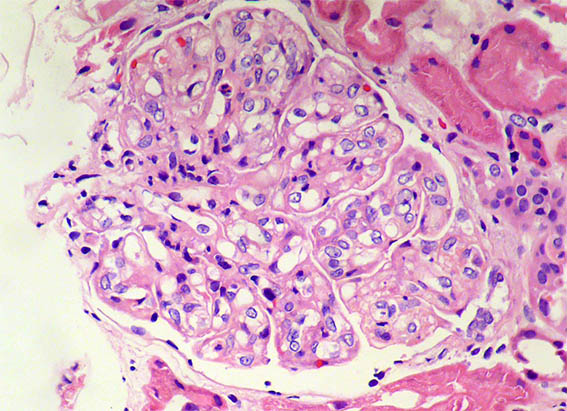

Figure 1. H&E, X400. Note the lobulation and hypercellularity, mainly mesangial in this image.